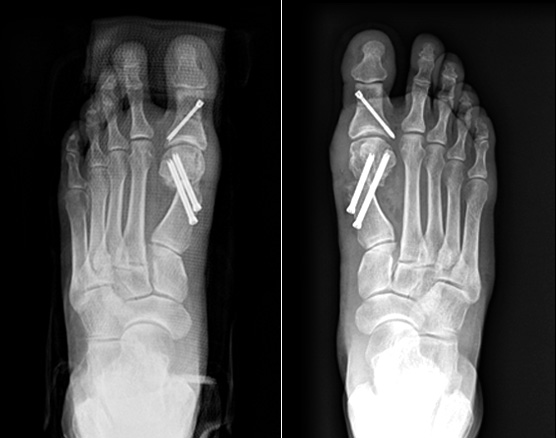

MICA, minimally invasive Chevron & Akin osteotomy

이전에는 무지외반 수술은 5cm 이상 피부를 절개하고 뼈를 싸고 있는 골막을 절개하여 수술을 하였습니다.

그래서 무지외반 수술은 통증이 심한 수술에 속하였지만

비절개 무지외반 교정술을 시행하고 나서는 획기적으로 회복 속도가 빨라졌고,

골막을 절개하지 않기 때문에 수술 후 통증도 많이 줄었습니다.

비절개 무지외반 교정술은 나사와 절골침이 들어갈 정도의 작은 구멍만 내고 하는 수술로 흉터는 낫고 나서는

거의 점처럼 보입니다. 수술 다음 날부터 큰 통증 없이 딛고 걸어 다니는 것도 가능합니다.